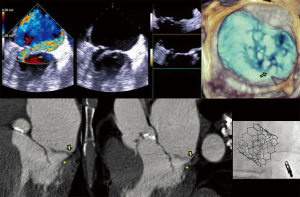

- CT, compared to echocardiography, lacks hemodynamic data, has lower signal to noise ratio, comparable temporal resolution and better spatial and contrast resolution, making it suitable for MV imaging (10). Operator-dependent, optimized imaging protocols for MV include: wide field of view, higher peak kV, bolus timing using time attenuation curves, left atrial contrast target, 5–10% phase intervals and specific reconstructions for annulus sizing and LVOT analysis (11). Image analysis is performed on the thinnest possible slice, using projections similar to echocardiographic views, with 4D reconstructions and multiplanar reformatting adjusted to minimize beam hardening and blooming effect. Lifelike, 4DCT cinematic rendering may be more useful compared to traditional 3D volumetric reconstructions. CT is indispensable for mitral annulus sizing and for the prediction and evaluation of LVOT obstruction risk in TMVR (Figure 3, Video 2) (10,12-22). Additionally, CT allows precise measurement of the geometric mitral valve area, predicts optimal fluoroscopic angles and identifies the location of the coronary sinus in relation with the annulus (Figure 4). Accurate sizing of the MA is critical for device choice. The least square planes method projects the 3D contour of the annulus on to a 2D plane and led to the concept of a simplified, flat, D-shaped mitral annulus, which reflects the actual planar landing zone of TMVR devices (6,23,24). A reproducible “effective annular diameter” can be derived from either the measured area, or the perimeter of the annulus (12). CT is vastly superior to echocardiography in imaging mitral annulus calcification (MAC), which can disrupt the atrioventricular groove and extend into the leaflets or the adjacent myocardium. Extensive leaflet calcification or fibrosis represents the basis of “degenerative MS” (Figure 5). MAC may involve the adjacent myocardium, or display a “caseous” core, without significant MS (Figure 6). TMVR creates a “neo-LVOT” between the basal segment of the interventricular septum and the AML, displaced anteriorly by the prosthesis struts, or flange (25). The semilunar cross-sectional area of the neo-LVOT may be measured by planimetry. Since LVOT obstruction may have profound hemodynamic consequences, several methods have been proposed to predict the risk of this complication, including proprietary software (11,24-26). Predictors of LVOT obstruction can be identified by CT, TTE or TEE: aorto-mitral angle <110°, LVOT area <2.0 cm2, length of the AML, short chordae, direct papillary muscle attachment, thickness of the basal segment of the interventricular septum and LV cavity size.

- The Paravalvular Leak Academic Research Consortium expert statement describes endpoint definitions and the role of imaging (36). For mitral paravalvular leaks (PVL), TEE overcomes the left atrial shadowing from the prosthesis seen in TTE and precisely identifies the PVL location and size, allowing planning of the procedure and adequate communication with the operator. CT may identify prosthetic annulus dehiscence, incomplete sealing after TMVR, or early dysfunction of the prosthesis due to pannus, sometimes mimicking a PVL (Figure 8). CT imaging uses careful reconstructions, selected image kernels and multiphase analysis to evaluate the anatomy of the leak and the surrounding structures. A PVL may be serpiginous and be located under, rather than adjacent to, the prosthetic ring, requiring dedicated oblique views for accurate imaging. Additionally, their area is dynamic and may seal during various phases of the cardiac cycle (Figure 13, Video 5). This phenomenon impacts the evaluation of the severity of mitral regurgitation, as the regurgitant jet may not be holosystolic and PISA may overestimate its severity. Additionally, the extent of associated hemolysis may be out of proportion to the size of the regurgitant jet, as estimated by color Doppler. In patients with mechanical prostheses, TEE may predict the risk of disk impingement by the closure device and is used to determine the size of the closure device. Guiding the procedure, cropped 3D TEE and 2D X-plane views are used to ascertain the passage of the wire through the PVL orifice. Once the device is deployed, an immediate assessment of mechanical leaflet mobility is performed, followed by a search for residual leaks, frequently under hemodynamic stress (volume challenge and pharmacological manipulation of the arterial pressure). While PVL closure traditionally relies on a transseptal approach, a transapical “Hopscotch” approach has been described recently, which also benefits from echocardiographic intraprocedural guidance in combination with CT angiography (37).